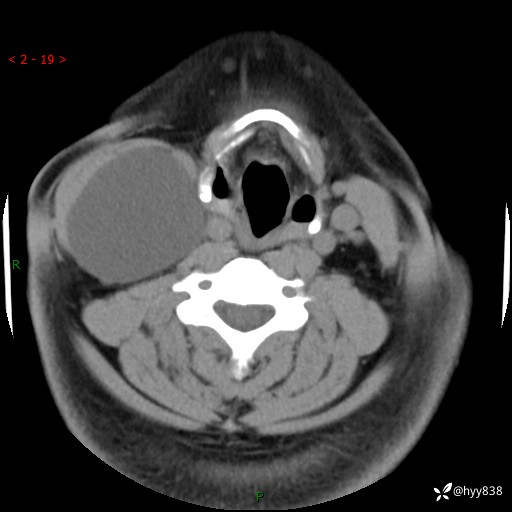

颈部CT平扫+增强